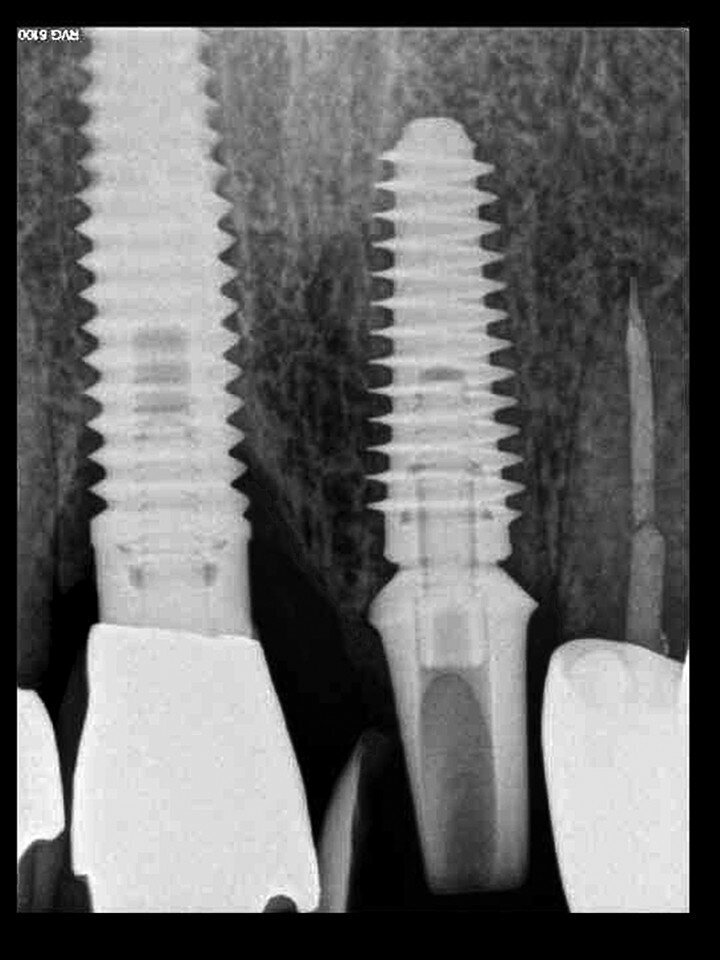

Fig. 26b: A post-op periapical radiograph confirmed successful sub-crestal placement of

this platform-switched design.

The initial plan was for immediate extraction, immediate placement and immediate restoration. Therefore, it was essential to measure the implant’s stability with an objective technology, RFA, which provides an ISQ value utilising an implant-specific SmartPeg (Osstell; MEGA ISQ, MegaGen). The baseline ISQ value (76) confirmed sufficient initial stability to place an immediate restoration (Fig. 25). The prefabricated CAD/CAM abutment was then secured to the implant, and a postoperative periapical radiograph confirmed successful sub-crestal placement for this platform-switched design (Fig. 26a). The transitional acrylic restoration was then placed and examined for any occlusal interferences (Fig. 26b). It was important that the restoration be out of occlusion to avoid premature forces that could complicate integration. The soft-tissue contours were excellent, and no sutures were required, since no flap was raised (Figs. 26c & d). After a period of eight weeks, the implant stability was measured to be at 80 ISQ, confirming that the integration process had continued to progress successfully and that the implant was ready for the definitive restoration. An intra-oral scanner and scanning abutment were then utilised to capture the position of the implant and soft-tissue emergence profile. The post- operative CBCT scan revealed the intact crescent shape of the root membrane (Figs. 27 & 28). The definitive restoration was then delivered and exhibited excellent retention of the soft-tissue profile (Figs. 29 & 30).